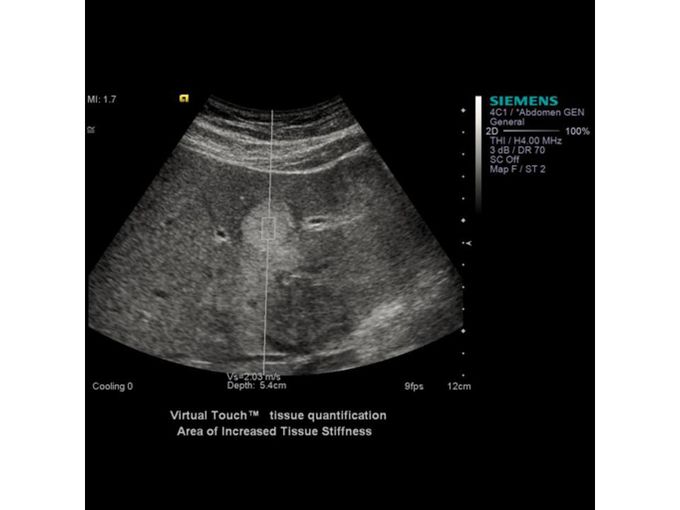

Кроме новой техники, можно заказать восстановленные медицинские системы: ультразвуковые сканеры, томографы, флюороскопы, ангиографы и хирургические установки С-дуга.